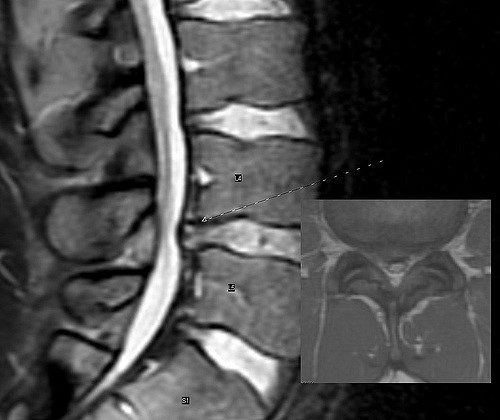

It is not uncommon for people to go to the emergency room when this first happens because the pain is so terrible. They are certain they have broken their back or something worse, but when the MRI shows a herniated disc, then people really start to have questions.

The discs in the spine are small, pillow-like devices that go between each bone (called vertebra) of the spine. Discs are filled with a jelly-like substance to prevent the bones from rubbing against one another and to prevent shock when you move around.

When too much pressure is exerted on the disc, it can bulge out to one side, like a tube of toothpaste if you press in the middle of the tube. If the bulge touches a nerve, it can cause pain, numbness, or a tingling feeling. If it doesn’t touch a nerve, you might not even know that the disc has been damaged.

If there is a sudden force or trauma exerted on the disc, such as in a car accident, or if the bulging disc is not allowed to heal and return to its proper location, the disc can herniate or slip. When people speak of a slipped disc, they are referring to a herniated disc.

Imagine stepping on one end of that tube of toothpaste. It would bulge and then split open, spitting out the contents. This is very similar to what a herniated disc does. When the material inside the disc touches a nerve (and it will) this can cause very intense, even excruciating pain.